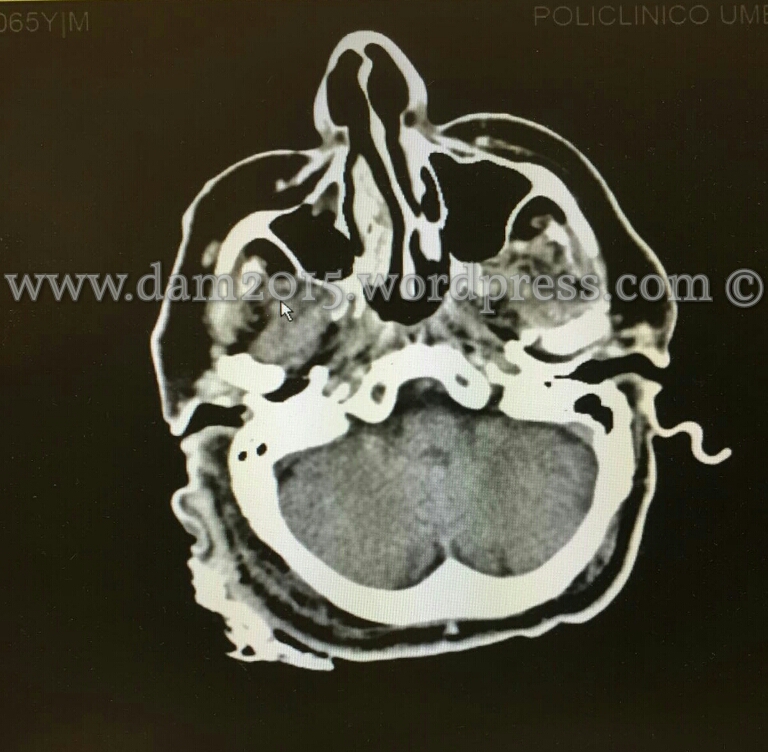

Esegue TC total body: negativa(si evidenzia ematoma dei tessuti molli extracranici in sede occipitale destra, con alcune bolle aeree nel contesto).